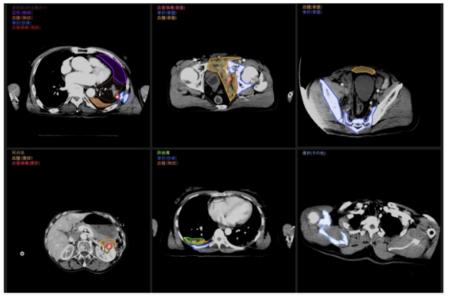

同社が開発した「ERATS(ER Automated Triage System)」は、肉眼で行っている外傷患者の全身CT検査結果の確認作業をAI技術で自動化。これまで数分を要していた重症度の判定時間を数十秒に短縮し、救急現場の作業負担を大きく軽減するなどの効果が期待されている。

ERATSは2025年から医療機器として正式販売される予定。同社はさらに、日本国内の救急現場向けに最適化した新型コロナの診断AIなどの開発プロジェクトにも取り組んでいる。